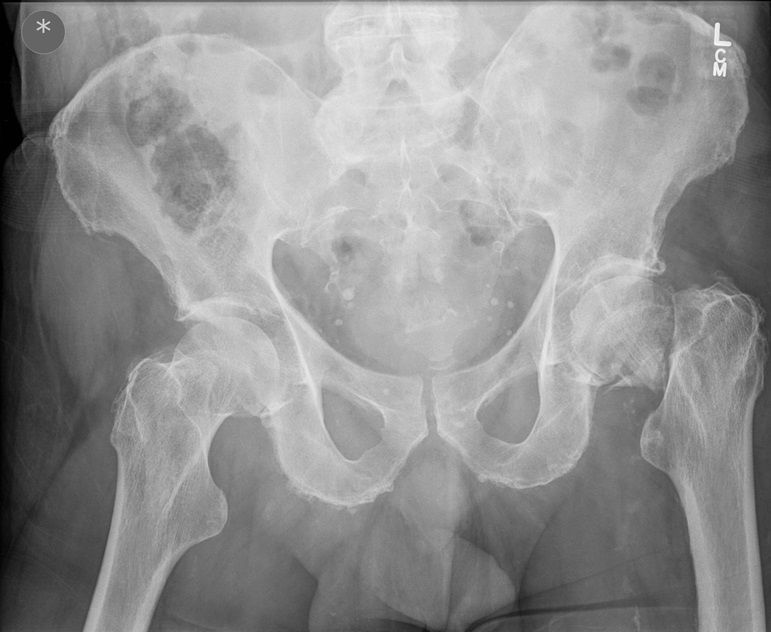

I was hoping you would partake in a study we are doing. We want to establish if there is any bias when deciding an operation based on the radiograph. We understand that the NICE guidelines state that the patient management for hip surgery should not be based on the radiographic findings; rather it should be based on defined criteria. However with that aside what we are requesting is that you look at the film + decide what operation either THR or Hemiarthroplasty. Click the dot + select answer.

Question 2

Question

Which operation would you perform?

Answer

• THR

• Hemiarthroplasty